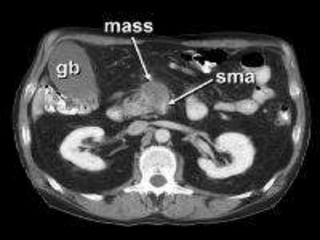

CT

 Focal or diffuse mass lesion which is hypo

dense (low attenuation) and hypo vascular

(poor contrast enhancement)

 Dilated MPD and CBD